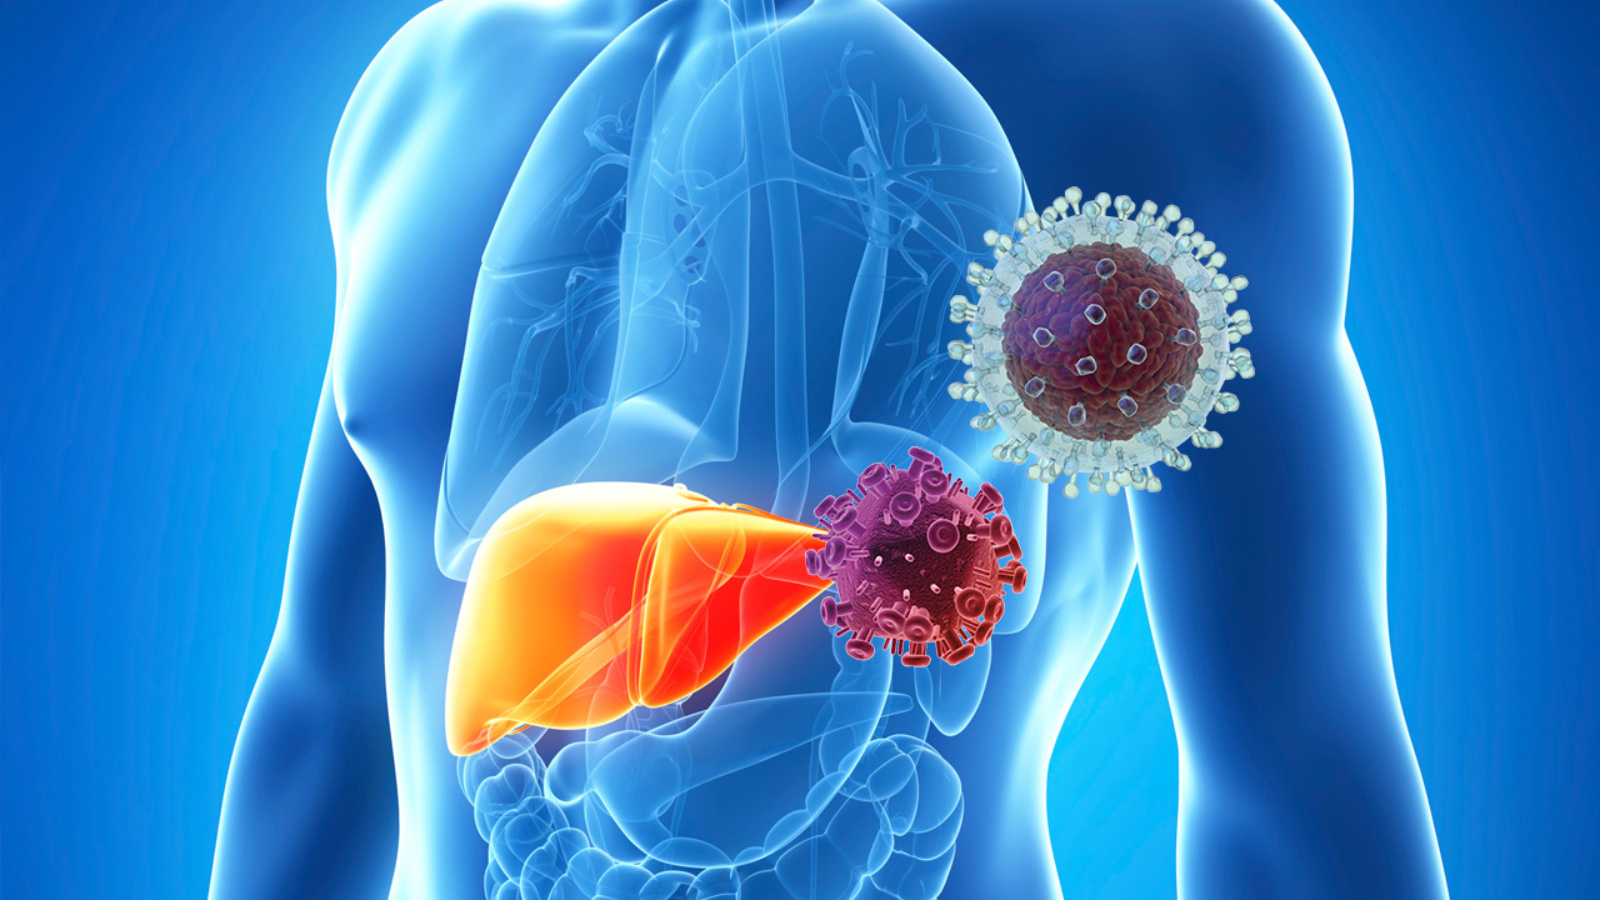

Изображения заболеваний печени: признаки и симптомы

Раздел: Пульс времени